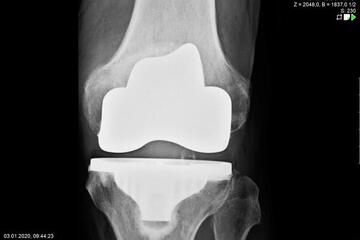

Endoprosthetics of the knee joint is an effective procedure for the treatment of symptomatic advanced wear and tear of the knee joint (gonarthrosis). If the X-ray shows a complete loss of joint space width under load, the complaints persist for more than 6 months, and the conservative therapy options have been exhausted, there is probably an indication for treatment with an artificial joint replacement (endoprosthesis). It must then be clarified which type of prosthesis is required, because today we have a large number of implants available. We distinguish between partial joints and full prostheses, and in the case of full prostheses we again distinguish between the degree of coupling of the prosthesis. If only parts of the joint are affected, only these have to be replaced and partial joints can be used. The so-called sled prostheses on the inner and outer side of the knee joint, as well as the sliding bearing replacement for problems on the kneecap, have both proven themselves effective. With full prostheses, we again differentiate between the degree of coupling of the prosthesis. Anterior and posterior cruciate ligament-supporting prostheses (surface replacement) partially coupled implants that support the inner and outer ligaments and coupled implants for complete loss of knee ligament and capsular function are used. Partially and fully coupled prostheses usually have to be inserted with stem components.

The knee prostheses are usually cemented in place, but cement-free implants are also available, which can be used, for example, in cases of cement allergies or very young patients.